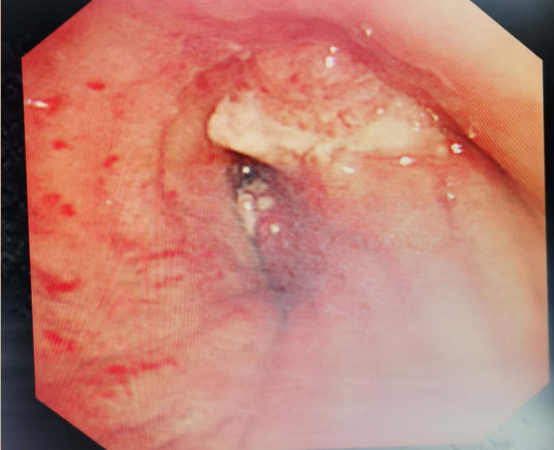

别看患者小吴年纪不大,可却已经是医院的“常客”了,近两年来,他已经门诊就诊78次,甚至连住院,都已经5次了。小吴第一次住院是在2018年9月。到呼吸内科病区住院时,护士们对他的第一印象就是非常“潮”,一枚单身小帅哥。但让护士们头疼的是小吴经常神出鬼没,一个不留神,人就不见了,总是偷偷溜出去抽烟。小吴的病也和吸烟有着千丝万缕的关系。27岁的他是因“咳嗽、咯血伴右胸痛2月余”入院的,入院后查胸部螺旋CT增强扫描提示:右肺中叶支气管开口区、下叶多发底段支气管增厚、狭窄,右下肺门强化肿块。起初医生还以为是特殊病原菌感染,但继续深入检查发现患者的右肺中叶支气管开口及右肺下叶基底段开口均可见新生物,予以活检病理,结果显示为“低分化癌”(表示肿瘤的恶性程度高,预后差),同时查出有骨转移,丧失了手术机会。记得病理切片出来的那天,小吴的父母是笑着来办公室的,可结果犹如晴天霹雳,让这个独生子女家庭瞬间飘摇在风雨中。母亲甚至嚎啕大哭,边哭还边骂:“这个不孝子,让他别抽烟别抽烟,还每天三四包地抽……”呼吸内科副主任陈腊青询问病史后发现,小吴家里没有恶性肿瘤家族史,父母、祖父母(二系三代)也都身体健康,自己也是小白领一个,没有特殊职业暴露史,所以致病主因就是吸烟。幸好,经过基因检测,小吴获得了靶向治疗的机会,一直服药治疗,生存期已达17个月。半年前小吴还出现了脑转移,目前病灶虽然控制稳定,但是他已经丧失了劳动能力,生活质量很差,并且随时可能复发。烟草和癌症据呼吸内科毛洪刚主任介绍,香烟燃烧的过程中可产生数千种有害物质,大致可分为6类:1.醛类物质:这一类物质主要对人体的呼吸道有很强的刺激作用。